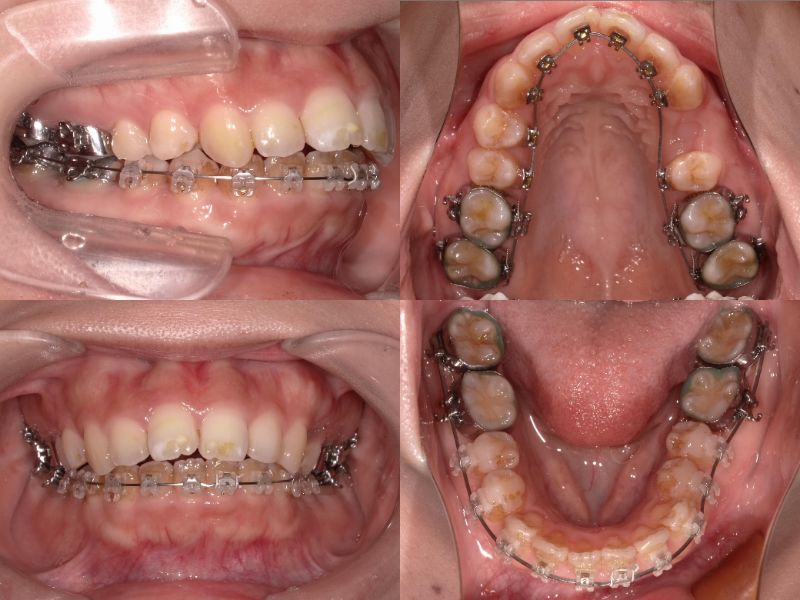

上下左右5番を抜歯し、上顎6番を口蓋正中縫合部からアンカースクリューで固定。

さらに、上顎2・3番の間に埋入したアンカースクリューから前歯を圧下し、口元の突出感とディープバイトの改善を図りました。

上顎6番を口蓋正中縫合部からアンカースクリューで固定し、さらに上顎2・3間に埋入したアンカースクリューから前歯を圧下しました。

この症例では、上顎前歯唇側にアンカースクリューを2本埋入し、上顎前歯の圧下を行うことでリスクをコントロールしました。